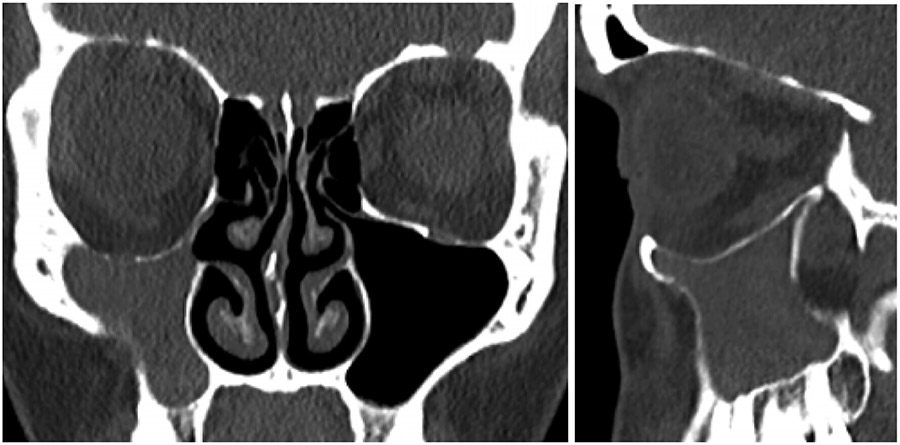

The patient reported a progressive, painless descent in her right eyeball over the last seven months, with no history of facial trauma or nasosinusal disorders. Clinical examination revealed enophthalmos, vertical dystopia and upper eyelid sulcus asymmetry (Fig. 1). Facial CT scan revealed a decreased right maxillary sinus volume with increased right orbital volume, downward displacement of orbital floor and collapse of the maxillary sinus (Fig. 2). Thus, a diagnosis of SSS was made based on the clinical and radiological findings.